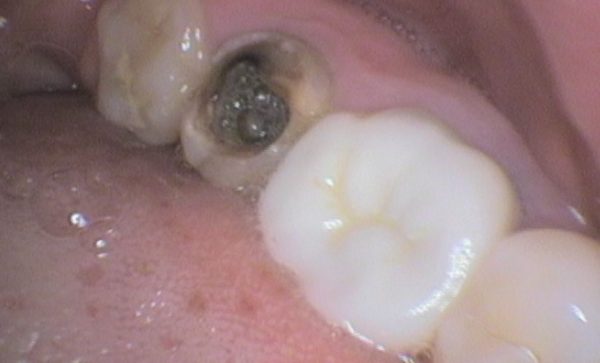

Case 20